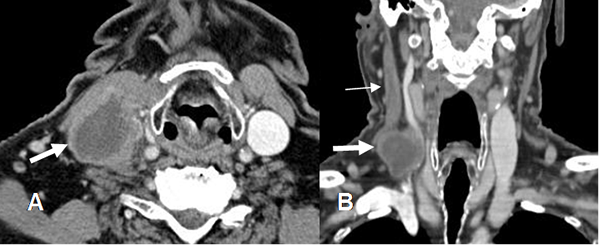

Fig 12. Tumor metastásico.

A: TAC axial y B: TAC reconstrucción coronal con contraste. Adenopatía necrótica en el cuello, secundaria a metástasis de un tumor escamoso. Adicionalmente hay trombosis de la vena yugular. (Flecha delgada).